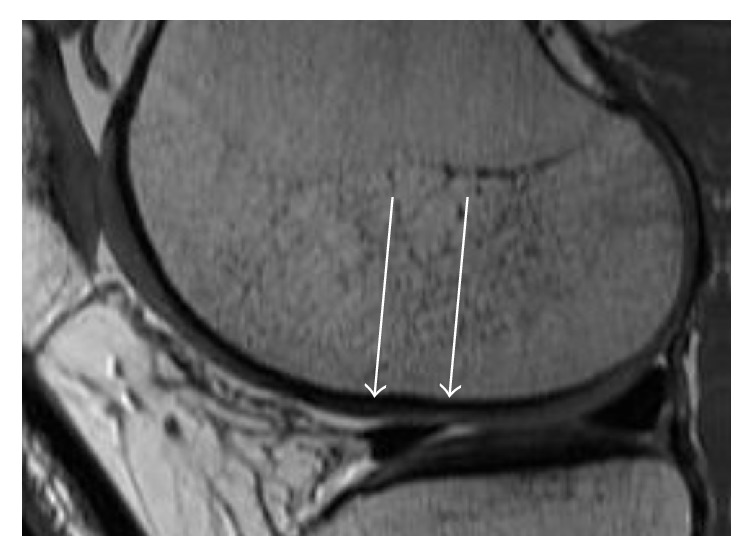

There was no hypertrophy of cartilage replacement tissue in any defect (Figure 4). The majority of patients (n = 8) showed a defect filling more than 50% with an intact surface of the AMIC plastic. In six cases, the cartilage restoration tissue was completely integrated in the surrounding tissue. Six patients showed an isointense signal intensity of the cartilage replacement tissue with a homogeneous structure to the surrounding tissue.

Figure 4.

Example of MRI with sagittal orientation (1.5 T) 14 months after the AMIC procedure. In the proton density weighted sequence, the defect filling is almost complete (see with arrows) with a good integration of the reparative tissue.